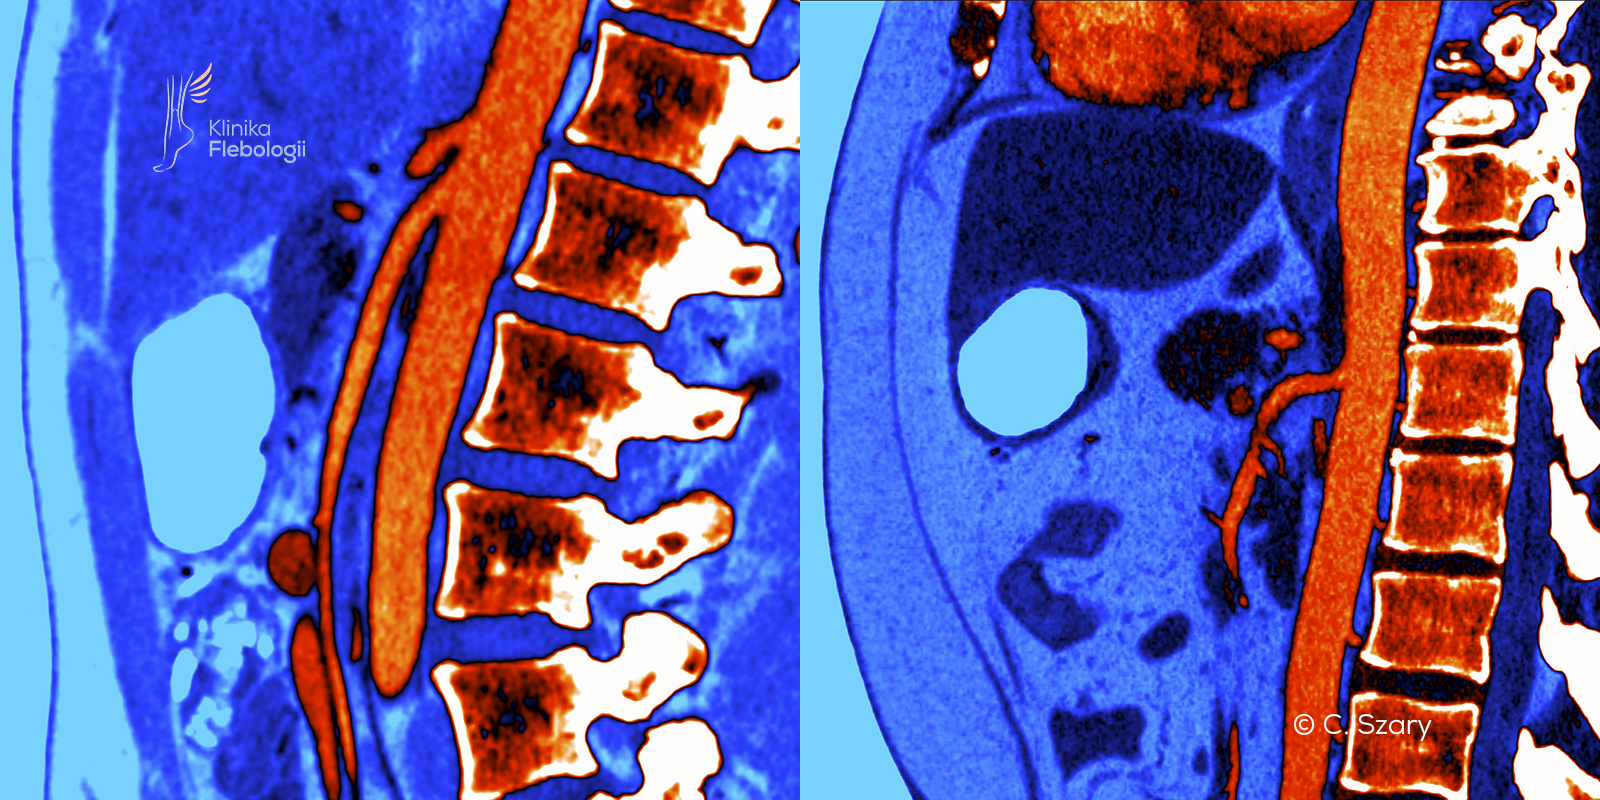

Zespół dziadka do orzechów związany jest ze zjawiskiem zaburzonego odpływu krwi żylnej z obszaru spływu lewej żyły nerkowej. Do ucisku lewej żyły nerkowej dochodzi najczęściej w miejscu jej krzyżowania na poziomie tętnicy krezkowej górnej (wariant przedni) lub w przypadku jej zaortalnego położenia (wariant tylny).

Zjawisko dziadka do orzechów należy do najczęstszych pierwotnych wariantów uciskowych na spływy żylne w organizmie człowieka. Najczęściej obserwujemy je na poziomie skrzyżowania lewej żyły nerkowej i tętnicy krezkowej górnej tuż pod jej odejściem od aorty brzusznej.

Anatomiczne zjawisko "dziadka do orzechów" polega na zaburzeniach odpływu krwi żylnej na poziomie spływu lewej żyły nerkowej. Związane jest ono z szeregiem objawów klinicznych, które wynikają z zaburzeń przepływu krwi w samej żyle nerkowej oraż żyłach do niej uchodzących, takich jak: żyły jajnikowa (lub jądrowa) czy żyły przykręgosłupowe.

Zespół dziadka do orzechów typowo powstaje w sytuacji, gdy tętnica krezkowa górna pod bardzo małym kątem odchodzi od aorty brzusznej, tylko nieznacznie się odchylając i wyginając. Sytuację pogłębia zazwyczaj uwydatniona lordoza lędźwiowa.